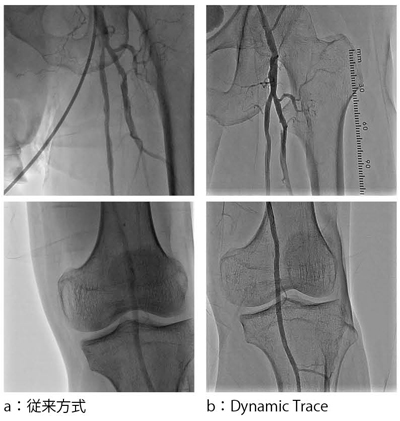

末梢血管への画質も追究している。下肢血管撮影では,直接線の影響でハレーションを引き起こしたり,線量不足を引き起こす。そのため,骨にかかる血管像の描出能が低下する。適正な線量を確保し,安定した画像を得るため,Dynamic Traceというコンセプトを打ち出した。これにより,カテーテルテーブルを移動させながら撮影する場合でも,安定した血管像を得ることが可能となる。図6に,従来画像との比較を示す。

図6 同一患者さんにおける下肢撮影像の比較 撮影日,造影剤量は異なる。

図6 同一患者さんにおける下肢撮影像の比較

撮影日,造影剤量は異なる。